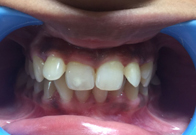

(7) Clinical Case-Veneer

Before Treatment

After Treatment

This female patient, with age 28 yrs came with a complaint of dirty teeth and an unaesthetic tooth in upper front left side of mouth. The patient has been treated with a thorough oral prophylaxis followed by veneering of the tooth.